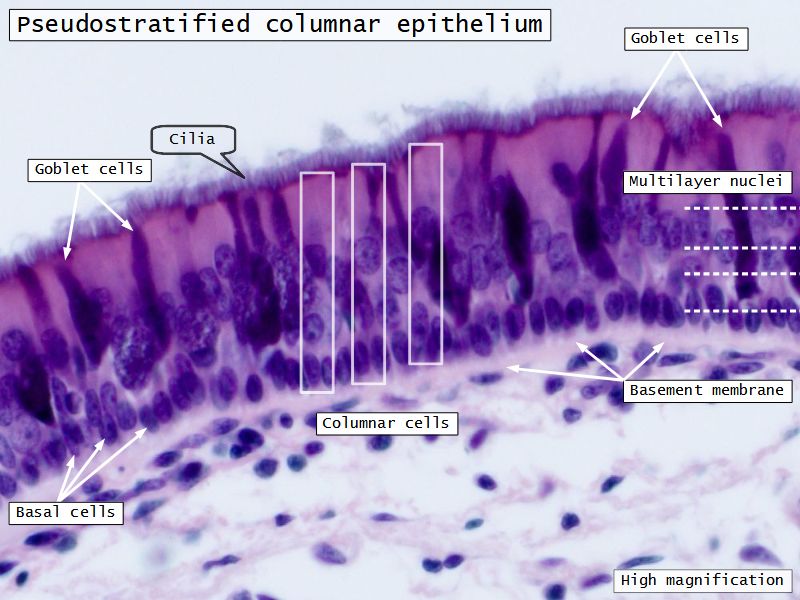

Respiratory epithelium

- Pseudostratified

- Ciliated

- Columnar

- Epithelium with

- 4 Cells

- Ciliated columnar cells

- Non-ciliated columnar cells

- Goblet cells

- Basal cells